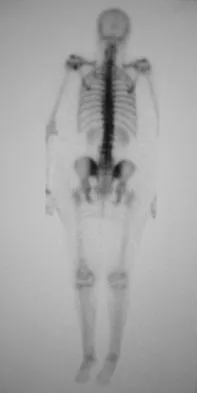

An 82-year-old woman reports activity-related knee pain. History reveals that she underwent total knee arthroplasty 16 years ago. AP and lateral radiographs and a bone scan are shown in Figures 38a through 38c. What is the most likely diagnosis?

Explanation

The radiographs reveal a large femoral metaphyseal lytic lesion with well-defined borders. Joint space narrowing medially is consistent with polyethylene wear. The most likely diagnosis is particle-mediated osteolysis. Metastatic tumors and primary sarcomas adjacent to an arthroplasty are extremely rare. In addition, malignant tumors and infection would more likely reveal a destructive lesion with poorly defined borders and increased uptake on a bone scan. Stress shielding with massive bone loss has not been described in knee arthroplasty literature, although this entity has been observed in fully porous-coated femoral implants in total hip arthroplasty. Robinson EJ, Mulliken BD, Bourne RB, et al: Catastrophic osteolysis in total knee replacement: A report of 17 cases. Clin Orthop Relat Res 1995;321:98-105. Archibeck MJ, Jacobs JJ, Roebuck KA, et al: The basic science of periprosthetic osteolysis. Instr Course Lect 2001;50:185-195.